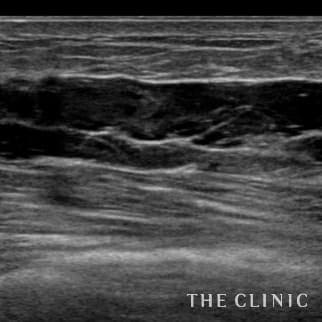

乳腺専用エコーを導入

術前後にエコー検査を行い、手術計画や結果についてを専門的に判断します。